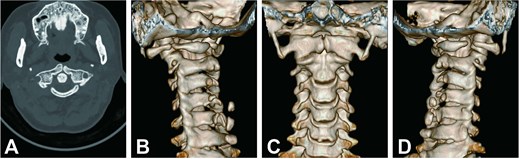

Cervical radiographs revealed hypoplasia of C1 but no evidence of atlantoaxial dislocation (Fig. 1). CT scans indicated bilateral bone abnormalities on the lateral sides of the posterior arch, particularly on the left side, with a midline cleft of the anterior arch (Fig. 2A). Three-dimensional reconstruction further demonstrated this abnormality (Fig. 2B–D). T2-weighted MRI revealed an intramedullary high signal at the C1 level, but no compression of the cord was observed (Fig. 3A and B). Cervical flexion-extension imaging indicated minor stenosis of the upper cervical spinal cord in the neck flexion position, but this alteration was not substantial (Fig. 3C–F). We considered that the high signal may be related to the repeated subtle activity of the posterior atlantoaxial arch in the past over a long period of time.

Cervical CT scan. (A) Axial CT image showing hypoplasia of the posterior arch and midline cleft of the anterior arch. (B–D) Three-dimensional reconstructed CT images showing atlas deformity from different views.